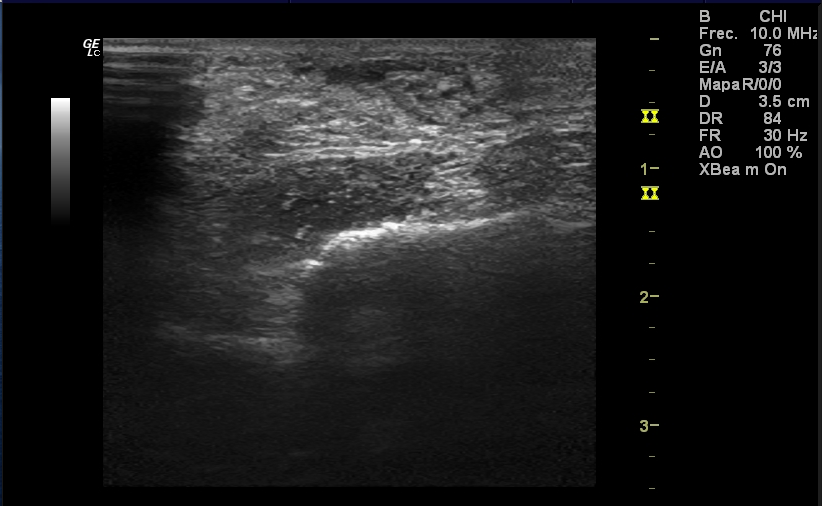

Hombre de 82 años alérgico a betalactámicos, dislipémico, hipertenso y EPOC, que es valorado en Urgencias por un cuadro catarral, tras el cual se ajusta medicación domiciliaria y se pauta levofloxacino 500 mg/día durante 5 días, ante la sospecha de reagudización con criterios de infección sobreañadida.Hallazgos ecográficos

Rotura del espesor completo de ambos tendones Aquíleos, a 4 cm del borde superior del calcáneo aproximadamente, con retracción del cabo proximal y GAP entre ambos cabos de 3 cm. No se ve derrame articular, aunque sí cierto edema de tejido celular subcutáneo.Pruebas complementarias